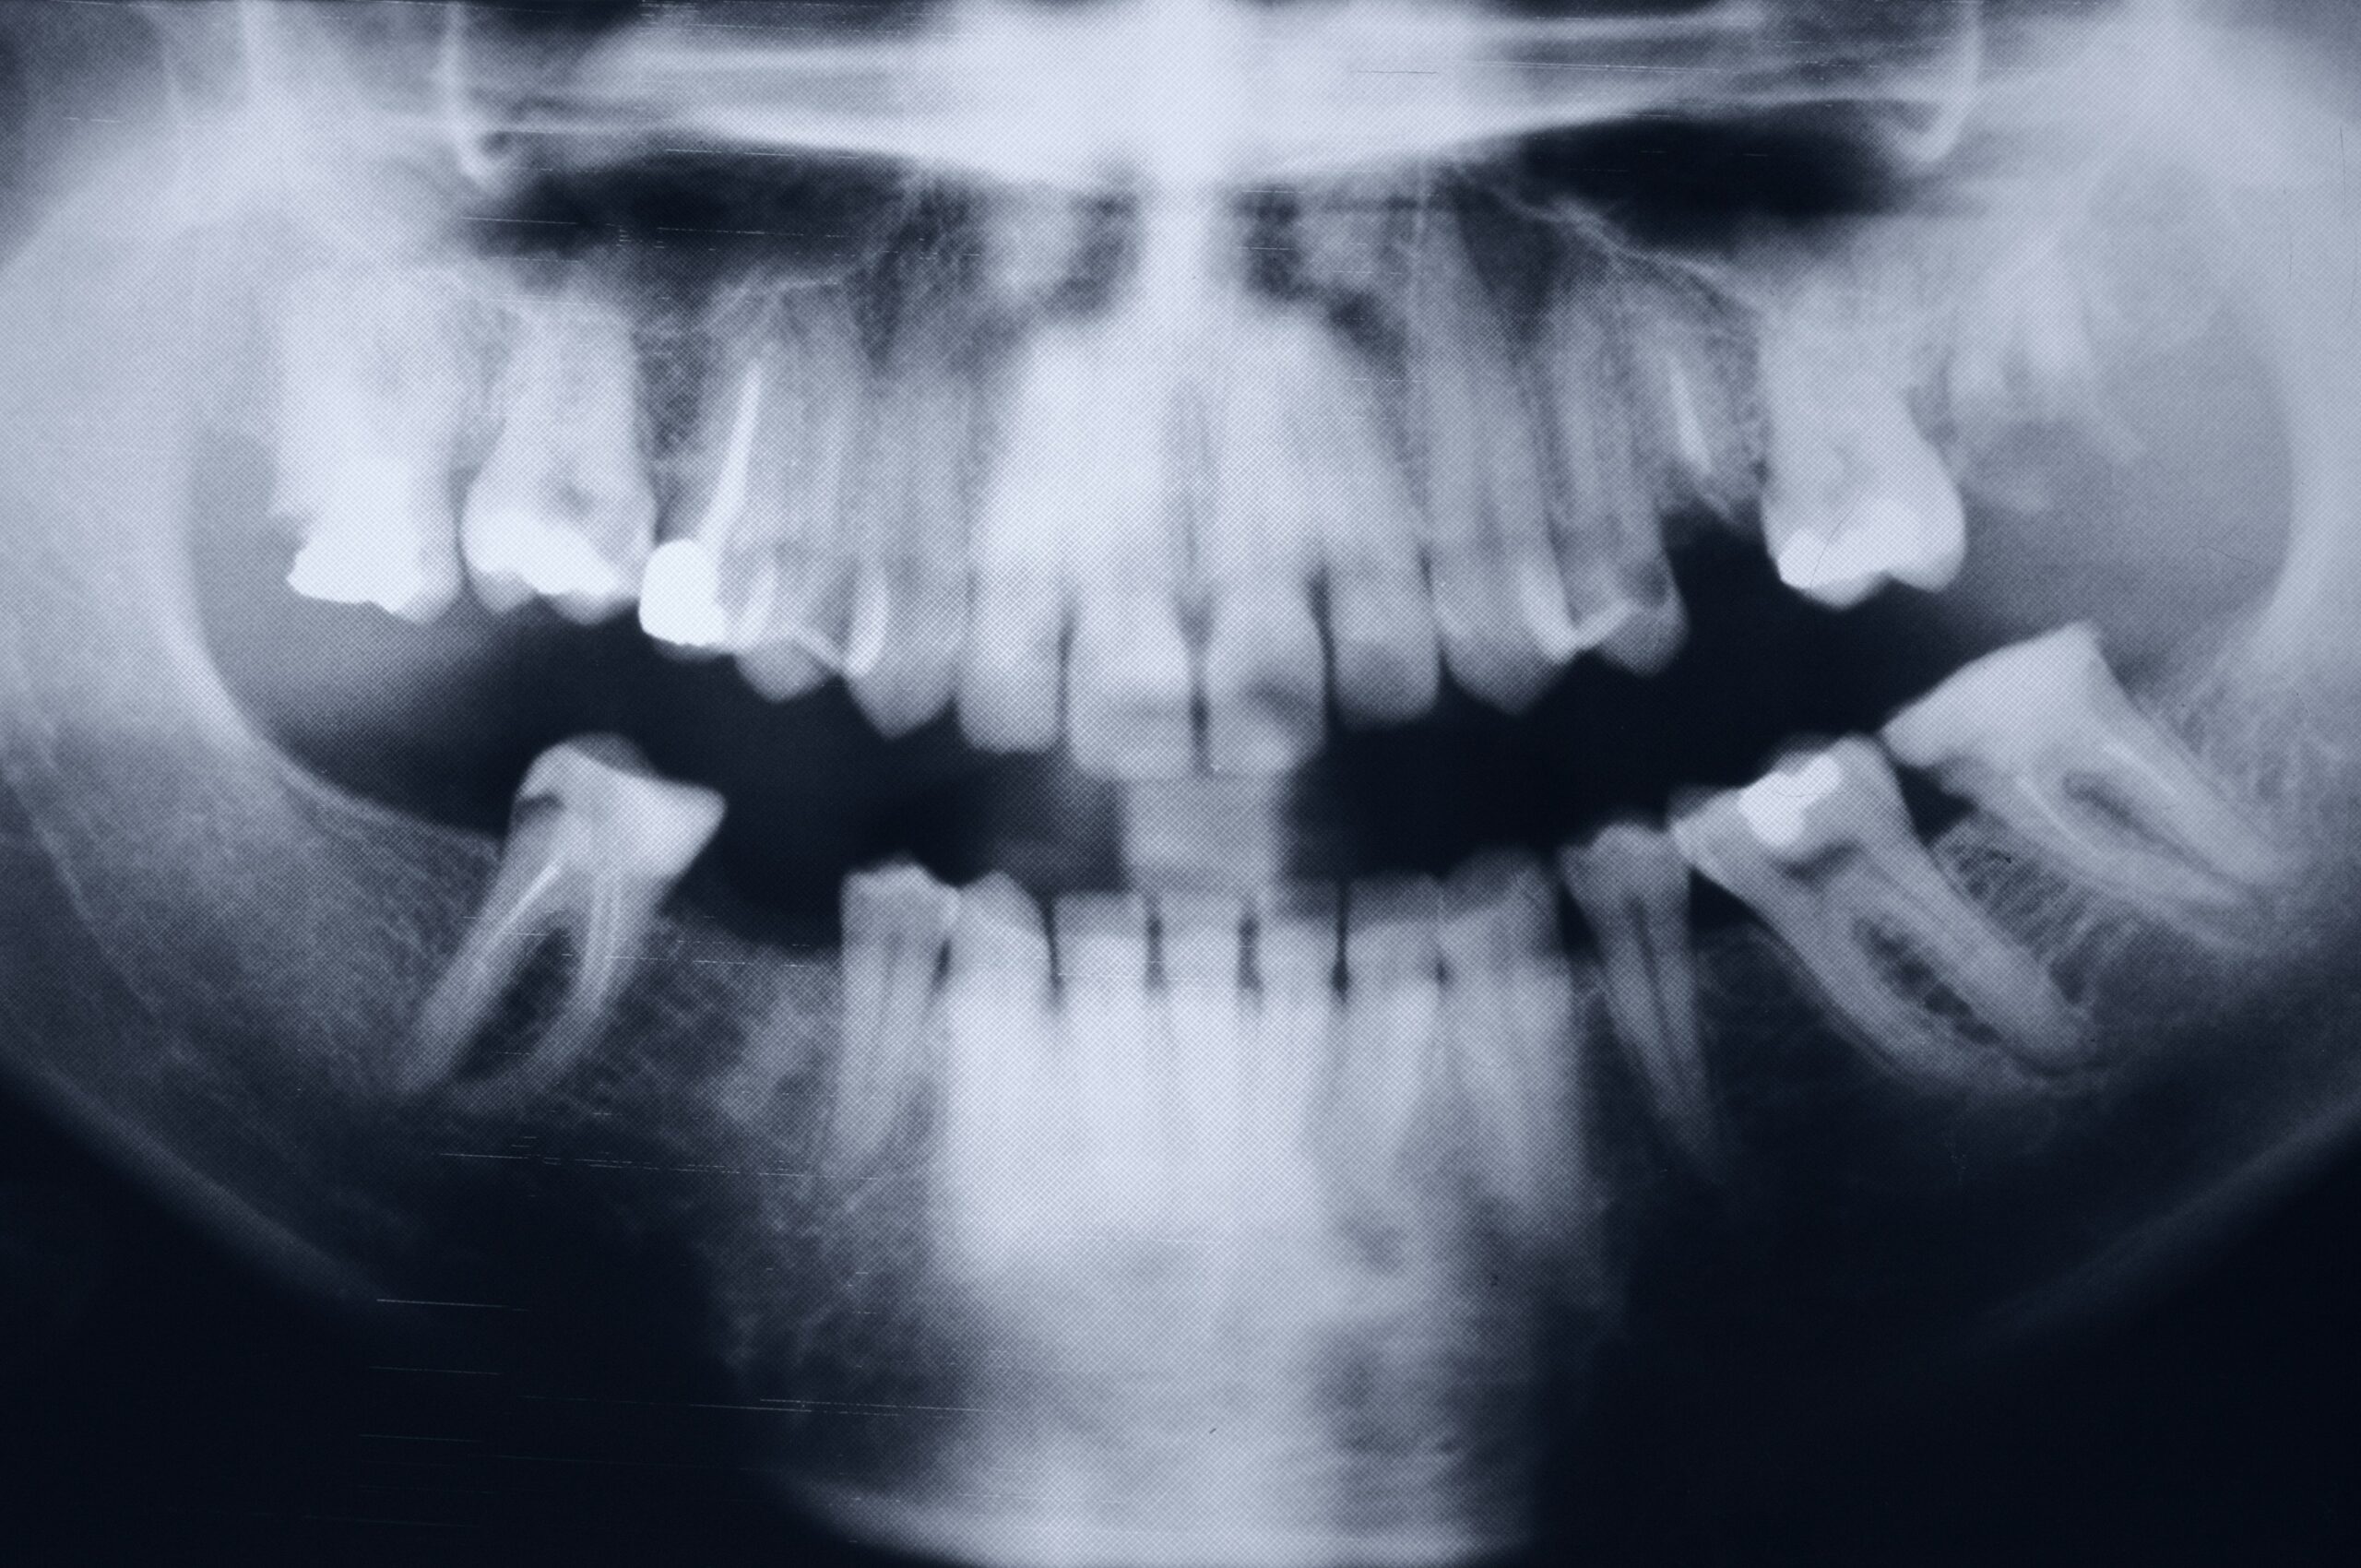

• Dépistage et bilan parodontal

Analyse clinique et radiologique pour évaluer l’état des tissus de soutien.